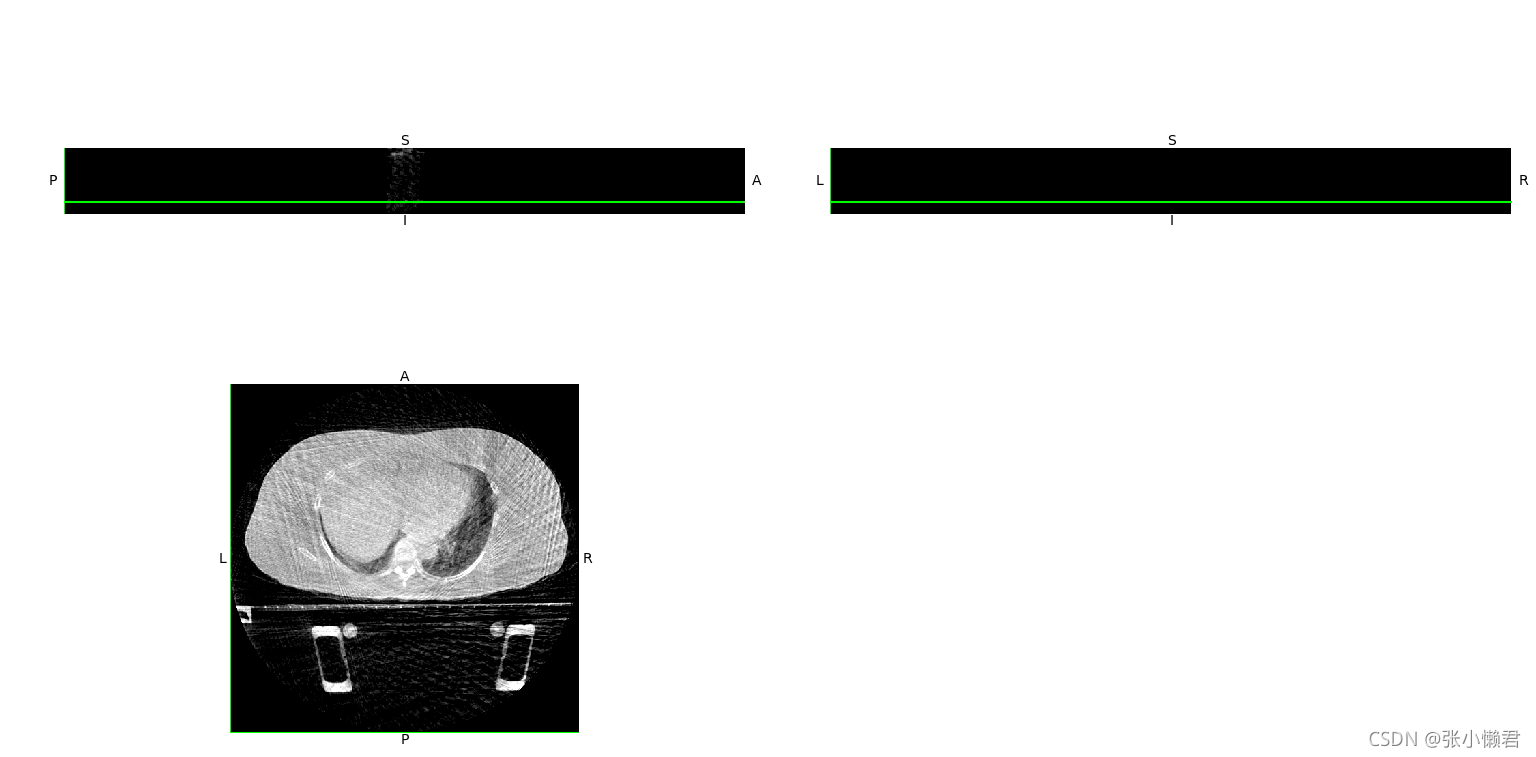

dicom2nifti.dicom_series_to_nifti(original_dicom_directory, output_file, reorient_nifti=True)(2)查看nii文件

import matplotlib

matplotlib.use('TkAgg')

from matplotlib import pylab as plt

import nibabel as nib

from nibabel import nifti1

from nibabel.viewers import OrthoSlicer3D

example_filename = './118PCTnii.nii'

img = nib.load(example_filename)

print(img)

print(img.header['db_name']) # 输出头信息

width, height, queue = img.dataobj.shape

OrthoSlicer3D(img.dataobj).show()

num = 1

for i in range(0, queue, 10):

img_arr = img.dataobj[:, :, i]

plt.subplot(5, 4, num)

plt.imshow(img_arr, cmap='gray')

num += 1

plt.show()